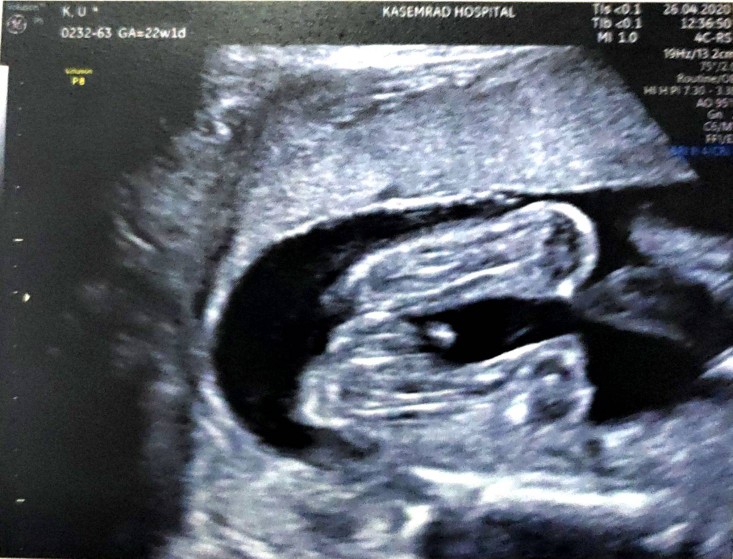

22 week ค่ะ